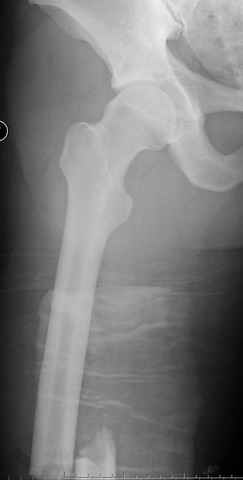

больному 42, автоавария, политравма, открытая черепномозговая травма, безсознании, открытый перелом бедра, размозжение мягких тканей, дефект кожи на передней поверхности бедра около 13 см2 от ожога, компартмент синдром.

По поводу открытого перелома больной ургентно взят на ретроградное интрамедулярное штифтование, после рутинного дебрайдмента и фасциотомии на бедре и на голени.

перелом бедра